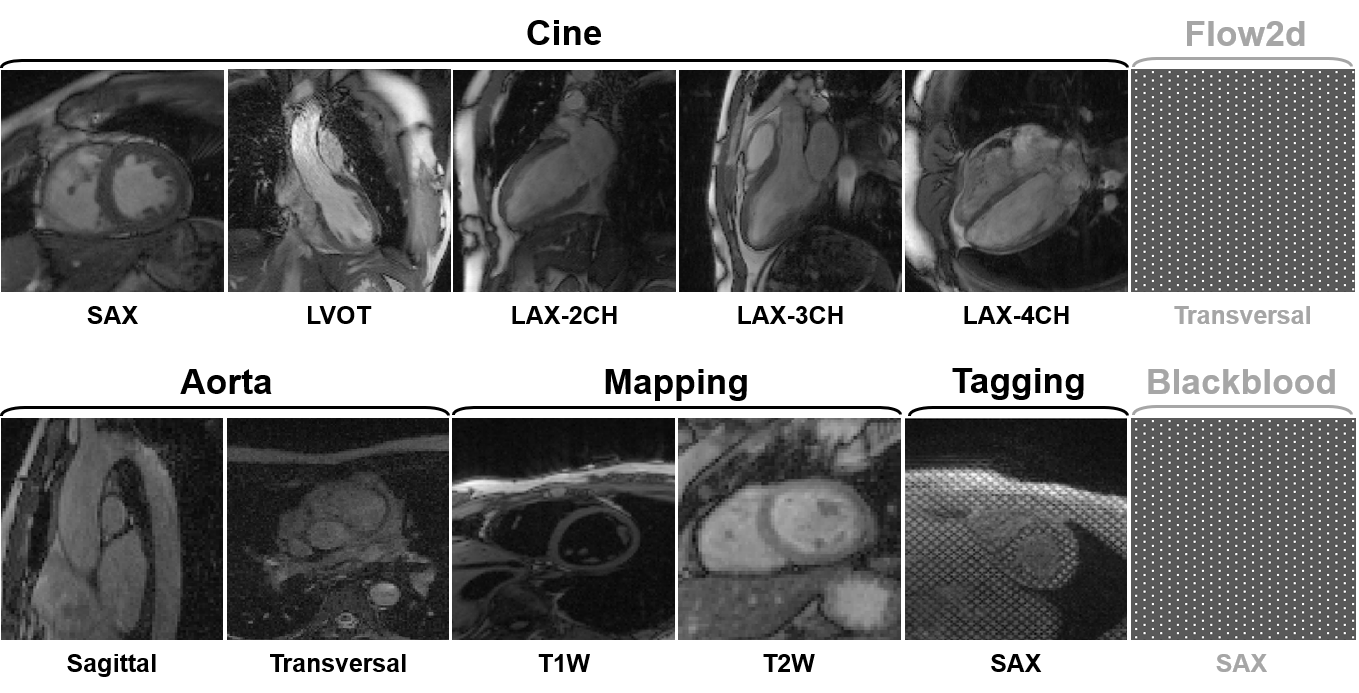

3) Dataset overview: The dataset will include multi-contrast k-space data, consisting of cardiac cine, T1/T2 mapping, tagging, phase-contrast (i.e., flow2d), and dark-blood imaging. It also includes imaging of different anatomical views like long-axis (LAX, including 2-chamber, 3-chamber, and 4-chamber), short-axis (SAX), left ventricul aroutflow tract (LVOT), and aortic (transversal and sagittal views).

4) Scan protocol: We use 'TrueFISP' sequence for cine, phase-constrast (i.e., flow2d), and tagging, and 'FLASH' sequence for T1/T2 mapping and dark-blood imaging. For T1/T2 mapping, signals are collected at the end of the diastole with ECG triggering. Typically, 5~15 slices are acquired for each contrast. The cardiac cycle is segmented into 12~25 phases with a temporal resolution of around 50 ms. Typical geometrical parameters include: spatial resolution 1.5×1.5 mm2, slice thickness 8.0 mm, and slice gap 4.0 mm.